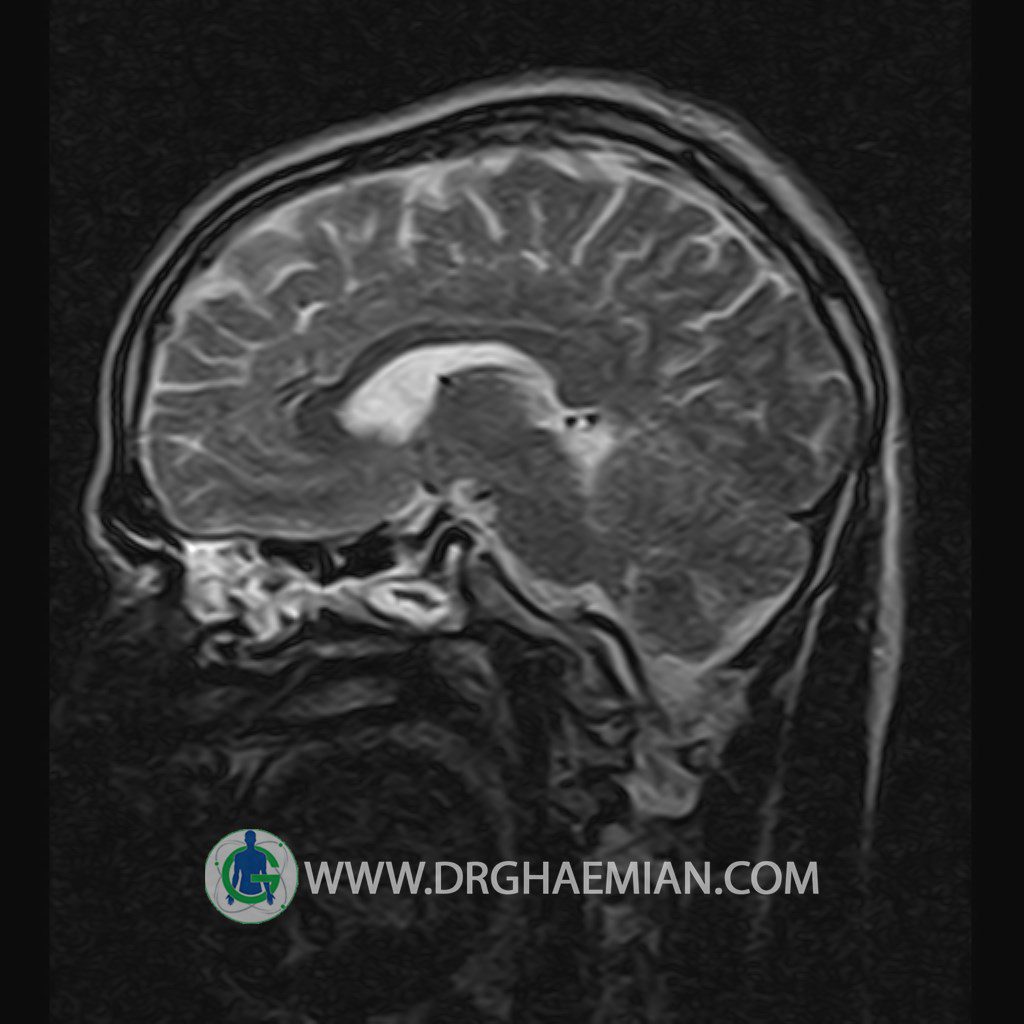

پزشکان اغلب از تصویربرداری ام آر آی برای تشخیص و درمان عارضه های پزشکی که فقط با استفاده از اشعه ایکس یا میدان مغناطیسی و امواج رادیویی قابل مشاهده است، استفاده می کنند. دستگاه ام آر آی تصاویر دقیق از ساختار های داخلی بدن ایجاد می کند. در این کیس یک میکروآدنوم در هیپوفیز بیمار مشاهده می شود.

HYPOPHYSIS MRI

(with and without contrast)

Technique: Axial , coronal T1 , Axial , coronal , sagittal T2 , Axial, coronal T1 post Gd & 64 dynamic thin coronal slices.

REPORT :

The infundibulum is centered and of normal size .

The optic chiasm and suprasellar spaces appear normal .

The cavernous sinus and imaged portions of the internal carotid artery and carotid siphon are unremarkable .

Evaluable portions of the neurocranium show no abnormalities .

The sphenoid sinus is clear and pneumatized .

Imaging of the hypothalamus after contrast medium administration was normal.

– Small hypoenhancing mass lesion ( 3 x 4 mm ) in posterior of pituitary stalk suggestive for micro adenoma

– Mucosal thickening in ethmoid & maxillary sinuses

is seen